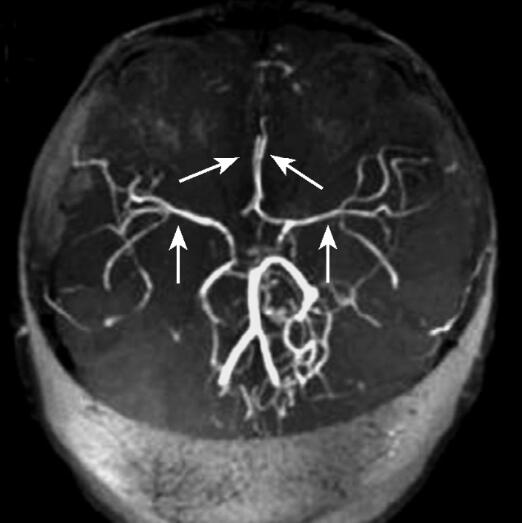

辅助检查:颅脑MRI(2010年11月17日):左侧额颞顶枕、脑干多发性缺血梗死灶。MRA:双侧颈内动脉未显示,后交通动脉代偿双侧大脑前动脉和大脑中动脉,大脑前动脉和大脑中动脉纤细;右侧大脑后动脉较对侧粗(图1、图2)。

图2 MRA(2010年11月17日)可见双侧颈内动脉未显示,双侧大脑前动脉、中动脉纤细(箭头)